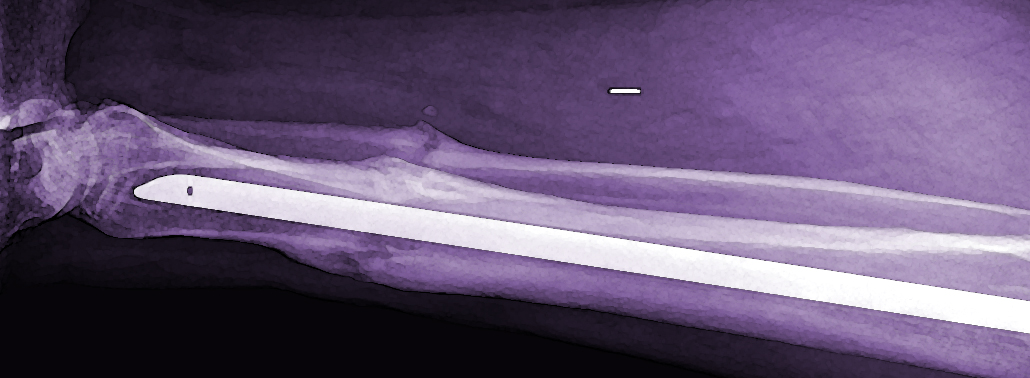

Se trata de un dispositivo empleado para fijar fracturas óseas en huesos largos. Consiste en una barra metálica (generalmente de aleación de titanio o de acero) que se introduce a través del canal medular, estabilizando el hueso desde el interior. Los clavos modernos suelen permitir, además, que se coloquen tornillos o pernos a su través por encima y por debajo del nivel de la fractura. A este procedimiento se le conoce como encerrojado del clavo y hace que la estructura sea estable en todos los planos del espacio.